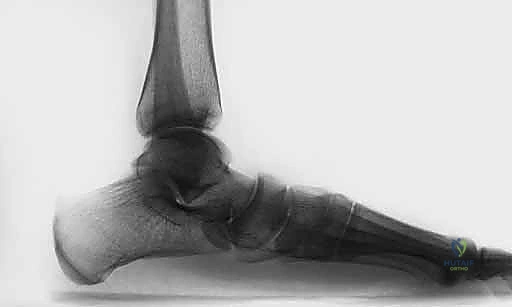

* الأشعة السينية أثناء الوقوف (Weight-bearing X-rays): وهي خطوة أساسية لتقييم زوايا العظام (زاوية ميري Meary's Angle، زاوية التغطية الكاحلية الزورقية Talonavicular Coverage Angle). تكشف هذه الأشعة عن مدى الهبوط والانحراف العظمي.